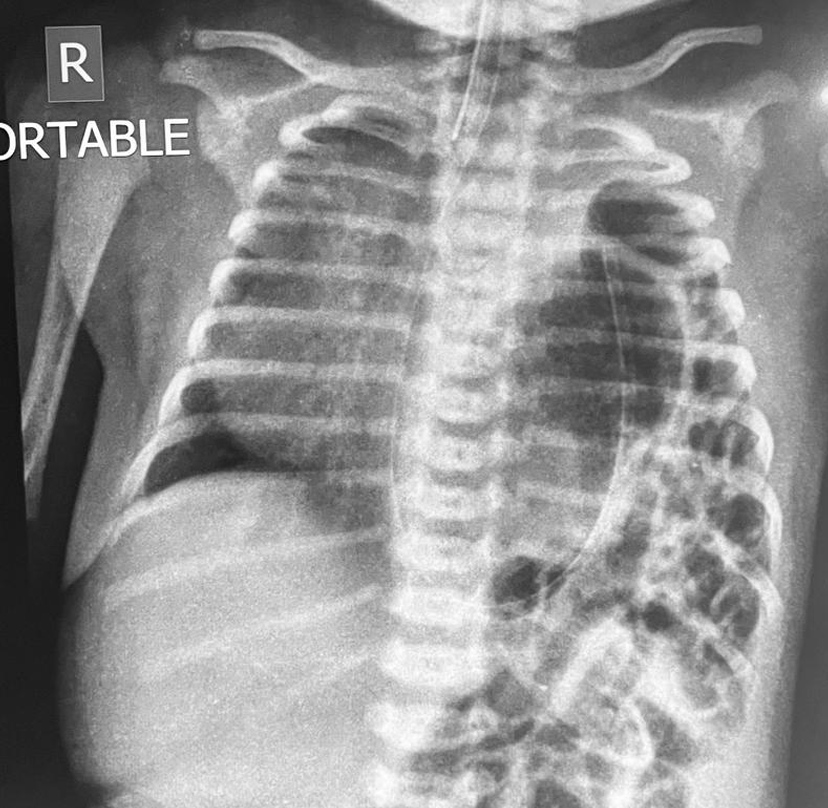

Diaphragmatic Hernia

When one or more of your abdominal organs protrude into your chest through a weakness (opening) in the diaphragm, this condition is known as a diaphragmatic hernia. Birth defects of this nature might also develop later in life. It's always a medical emergency that has to be fixed quickly with surgery.

A congenital diaphragmatic hernia (CDH) results from the diaphragm's improper development when the foetus is developing. One or more of the foetus' abdominal organs might migrate into the chest and take up residence where the lungs should be due to a malformation in the diaphragm. The lungs cannot adequately grow as a result. Most frequently, this just affects one lung.